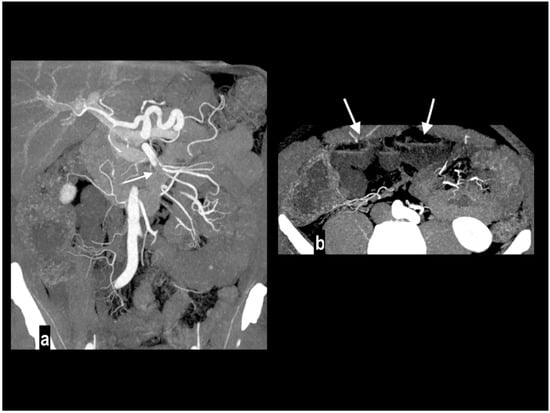

Nonocclusive mesenteric ischemia (NOMI) is an intestinal hypoperfusion in the absence of arterial or venous thromboembolism [2] accounting for up to 20% of cases of AMI [9,58], and atherosclerosis is not considered a risk factor [59]. The real incidence may be underestimated because this condition occurs in critically ill patients with predisposing conditions such as heart failure, major trauma, the use of vasopressors, and cardiogenic or septic shock (Figure 6) [2,42,60]. NOMI should be considered in the differential diagnosis in these patients because imaging findings may be subtle, and the distribution of the affected bowel may be discontinuous or involve multiple vascular territories [60]. The pathogenetic mechanism is poorly understood. It may rely on a protective reflex in which the mesenteric vessels undergo constriction or spasm to preserve blood flow to the cardiac or central nervous systems [2,3,21,42,61]. At CT, the diagnosis of NOMI can be challenging because vessels are not occluded and may present only a subtle luminal narrowing of SMA and its first-order branches. Segmental focal narrowing and dilatation (the so-called “string-of-sausages” sign) can be appreciated along mesenteric vessels. Although both the large and small intestine can be involved, characteristically, the bowel alterations are discontinuous and segmental. Other abdominal signs of the CT hypoperfusion complex can be appreciated such as a small-caliber aorta, a collapsed inferior vena cava, bowel mural hyperenhancement, and a hyperenhancement of the kidneys and adrenal glands [2,6,11,17,19,60]. Parenchymal infarcts are often associated with NOMI.

Figure 6.

NOMI. Diffuse stratified wall thickening of right colon ((a) circle) with patent mesenteric arteries (b). The 78-year-old patient had a severe systemic hypoperfusion and multi-organ failure, with bilateral kidney cortical necrosis ((c) circles) and ARDS. The patient died a few hours later.